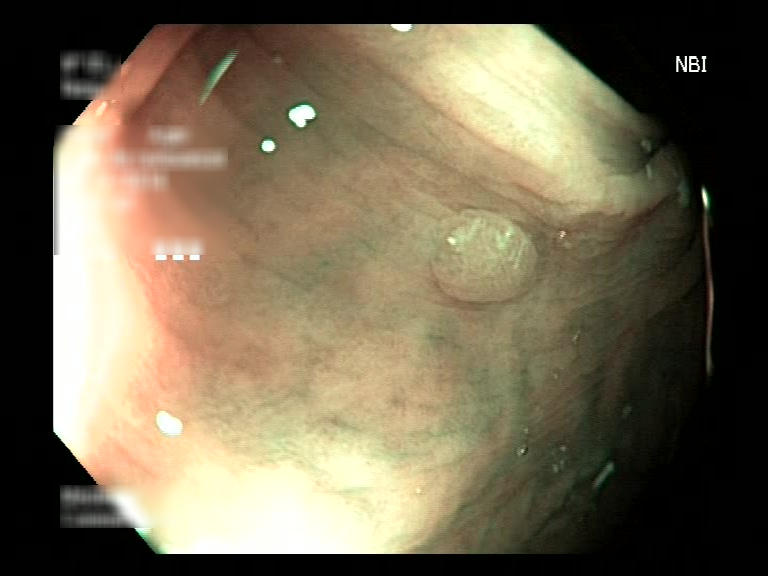

| Lesion | White Light Frame | NBI Frame | White Light Video | NBI Video | Camera Calibration |

| hyperplasic_01 |  |

|

WL.mp4 | NBI.mp4 | cam.xml |